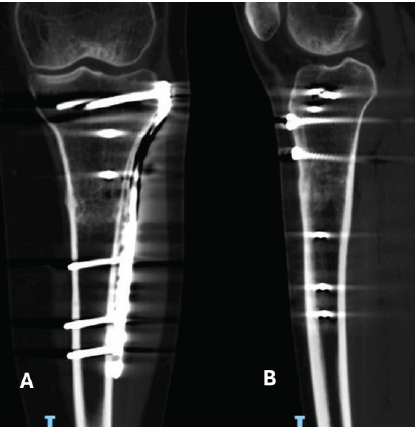

During the arthroscopic portion of the surgery in May 2023, a grade 1 chondral lesion on the lateral patellar facet was identified according to the Outerbridge classification, and lateral retinacular release was performed. During the second part, the tibial tuberosity (TT) was medialized by 1 cm and secured with two 4.5 mm lag screws, achieving a TT-TG distance up to 10 mm in the final measurement (Fig. 1).

Figure 1: (a) Anteroposterior and (b) lateral view of the left tibia immediately after tibial tuberosity osteotomy fixed with 4.5 screws.